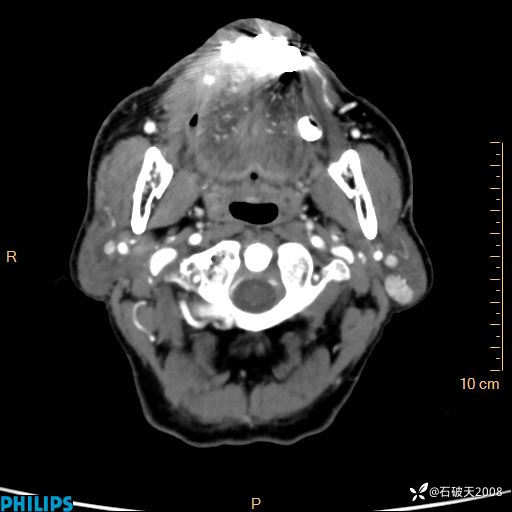

静脉期